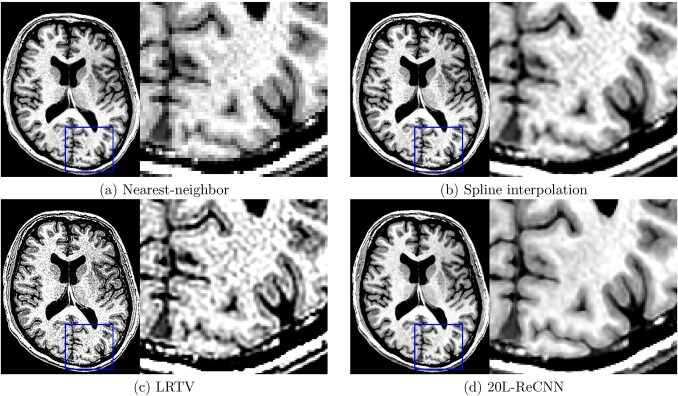

SISR